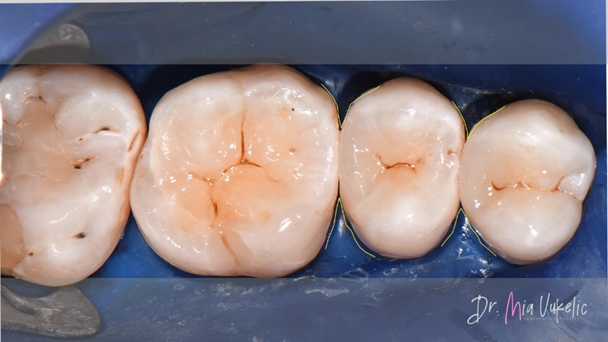

After the polishing process, the filling was coated with a surface liner (PermaSeal™ composite sealer, Ultradent Products). Occlusal and radiography control followed.

As it can be seen by the final pictures, Transcend composite offers an exceptionally esthetic appearance for the restoration. The Halo sectional matrix system allowed for a great proximal anatomy, as it can be seen on the radiograph.